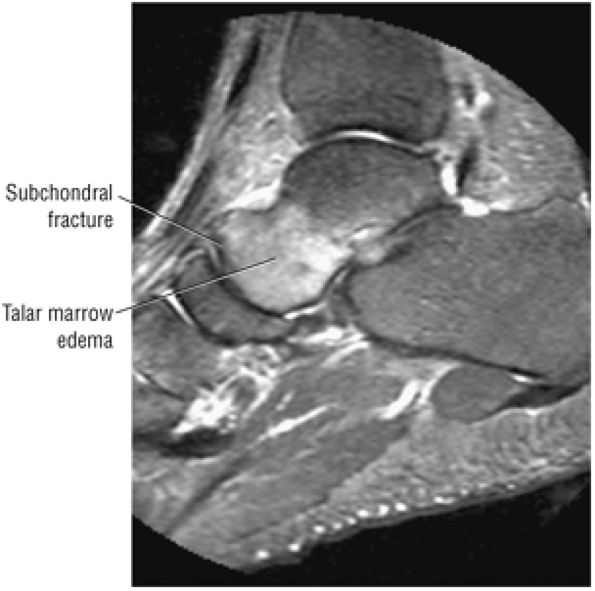

Stage I: Subchondral trabecular compression. Radiograph results are negative, bone scans are posi-tive, and marrow edema is seen on MR imaging (Fig. 5.95).

Stage IIA: A subchondral cyst (Fig. 5.96)

Stage IIB: Incomplete separation of the fragment (Fig. 5.97)

Stage III: Fluid around a nondetached, nondisplaced fragment (Figs. 5.98 and 5.99)

Stage IV: A displaced fragment (Fig. 5.100)